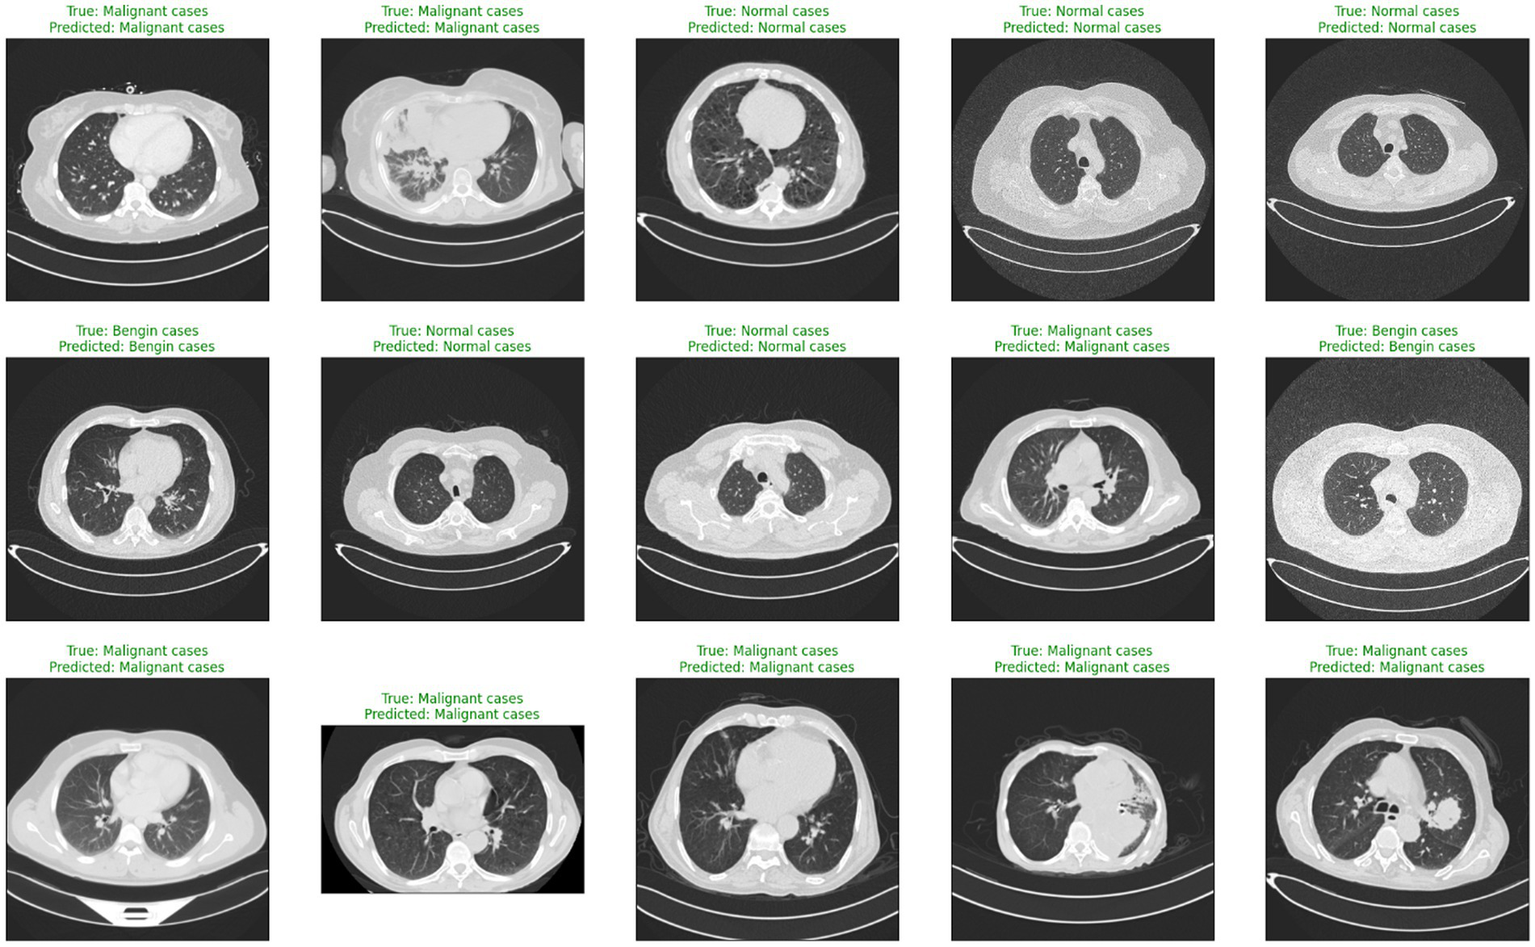

Deep learning (DL) and artificial intelligence (AI) have opened fresh opportunities to increase diagnosis accuracy in medical imaging (4). With a degree of precision usually approaching human ability, DL models especially convolutional neural networks (CNNs) have shown the ability to identify and comprehend small patterns in picture data (5). Nevertheless, the intrinsic opacity of such models limits their application in clinical practice as the human users of artificial intelligence systems sometimes find their decision-making process unclear or interpretable (6). Figure 1 shows a range of CT scans from the IQ-OTH/NCCD dataset (7, 8), therefore illustrating the range of cases used to train and validate the proposed classification system. The pictures show the range of lung cancer phases: benign, malignant, and normal events. These illustrations provide a graphic summary of the kinds of data used in this work to evaluate the EfficientNet-B0 model and for training.

Figure 1

Representative sample of CT images from the IQ-OTH/NCCD dataset.